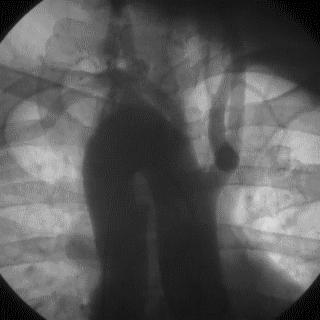

2014年,Patel T等首先采用球囊辅助通过技术(Balloon-assisted tracking,BAT),用于通过桡动脉途径中扭曲、细小节段(包括严重痉挛节段)(图1-2)。

图1

图2 BAT技术应用实例1。52岁女性患者冠脉严重痉挛(A),注射2次鸡尾酒后仍未缓解(B),采用BAT技术(C),顺利介导7F指引导管通过桡动脉严重痉挛节段(D)